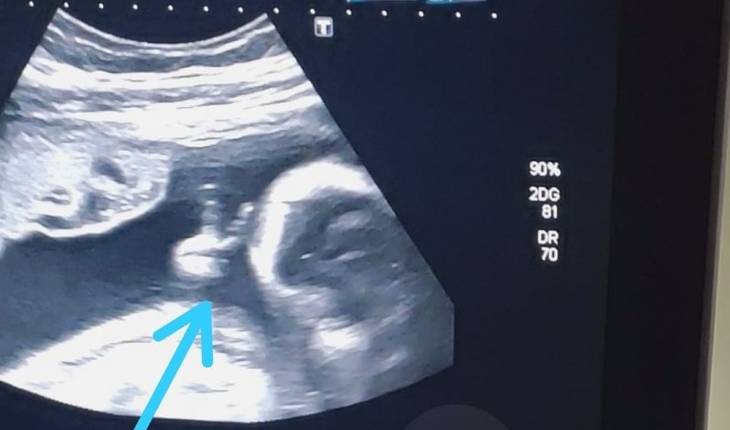

Para o pai, o ‘V’ feito pelo bebê simboliza um sinal divino de força, esperança e cura para a sua doença.